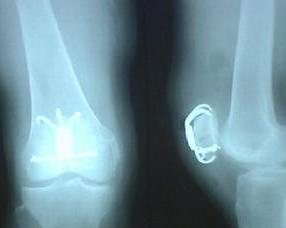

骨肉瘤又称为成骨肉瘤,是一种恶性骨肿瘤,多发生在20岁以下的青少年或儿童。骨肉瘤是从间质细胞系发展而来,由于肿瘤经软骨阶段直接或间接形成肿瘤骨样组织和骨组织使得肿瘤迅速生长。骨肉瘤在小儿骨恶性肿瘤中最为常见,约为小儿肿瘤的5%。骨肉瘤的突出症状是肿瘤部位的疼痛,因肿瘤组织浸蚀和溶解骨皮质所致。